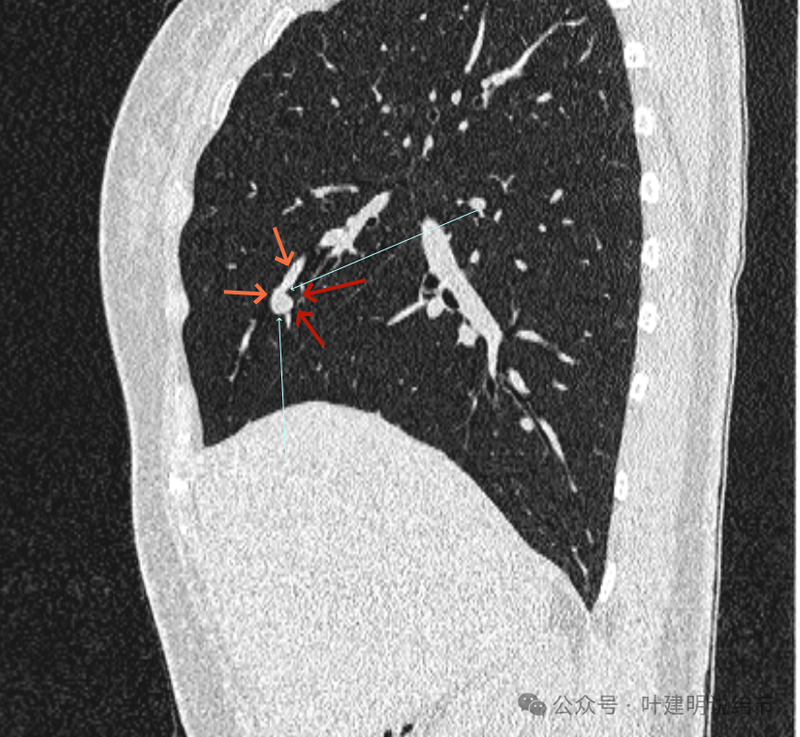

再看矢状位影像:

桔色的是血管,红色的是病灶,两者之间有间隙仍用天蓝色细线标注。

紧挨但仍有缝隙的。

血管贴着病灶,病灶表面略有毛糙之处。

血管有形成轻微血管弯征,两者紧贴。

两支血管夹着病灶,密度不同,有低密度间隙。

病灶与两侧血管关系均密切,明显觉得密度是不一样的,血管的密度略高,结节的略低。

病赤与血管在蓝色箭头处失去间隙,像是侵蚀血管壁,造成血管受侵犯破坏。病灶是软组织密度的,而且整体看有膨胀感。

病灶密度稍不均。表面不光滑。

病灶与边上血管间隙不清。

桔色箭头所示的血管受压稍有移位。

密度不同,关系密切。

边缘区域也是有膨胀感。

血管与病灶脱开后的样子。

边缘区也是基本上实性的。